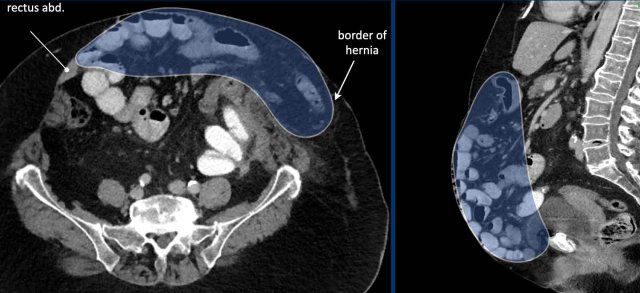

Image

In this patient the loss of domain is > 20% and additional strategies will be necessary to increase the abdominal capacity and compliance.

In this patient with a large hernia, the measurements are as follows:

• Hernia Sac Volume = (274 x 71 x 304 mm x 0,52) x 10-6 = 3.1 liter.

• Abdominal Cavity Volume  = (251 x 131 x 342 mm x 0,52) x 10-6 = 5.8 liter.

• Total Peritoneal Volume = ACV + HSV = 3.1 + 5.8   = 8.9 liter.

The loss of domain in this case is the volume of the hernia sac divided by the volume of the total peritoneal cavity:

3.1: 8.9 = 35%.

This is far greater than 20% and means that there is a high risk of complications during and after a simple abdominal wall repair.